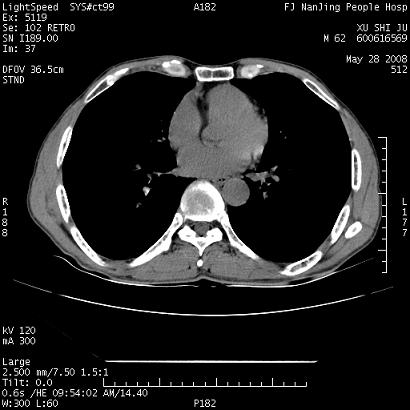

以下是引用lrj在2008-5-28 21:10:00的发言:[br]所示应该是正常结构,是对称的,多个层面都有!也不像是内乳动脉或是肿大淋巴结![br]右下肺渗出性病变伴空洞形成,其洞内见一结节,以下诊断都有可能:1 右下肺曲菌感染, 2右下肺结核空洞形成伴曲菌感染!3右下肺结核空洞伴壁内占位形成,虽说后者发生的几率很低 但作为我们应该多考虑一下吧!最重要的结合临床